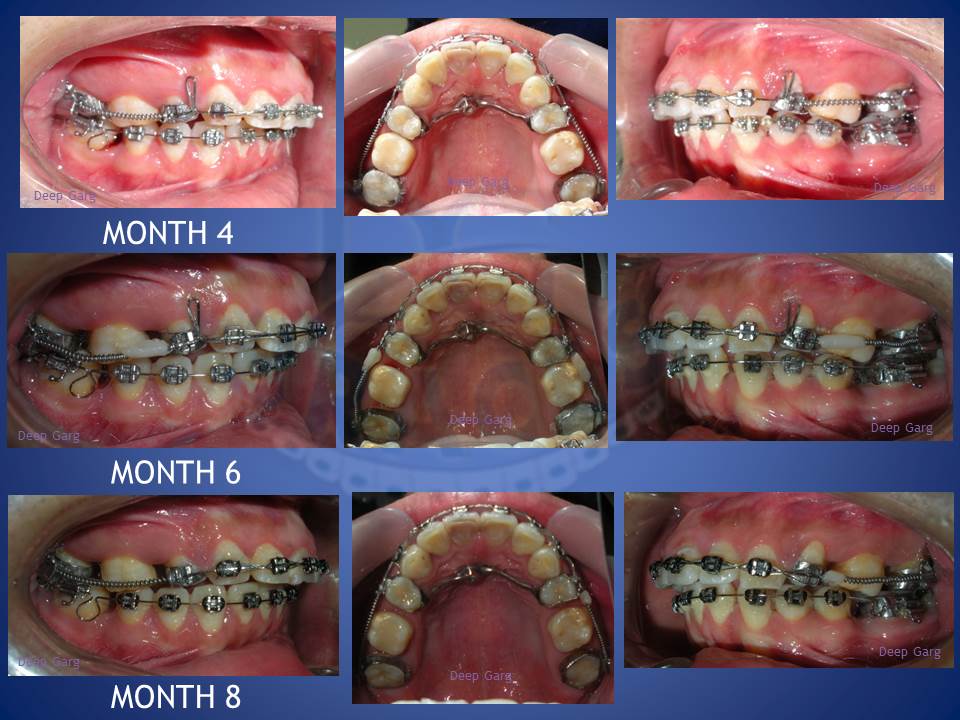

3.Molar distalisation though difficult can be very well done in cases where excessive spaces are required and no extractions can be afforded. Here a palatal Miniscrews was used and distalisation was done with coil springs.